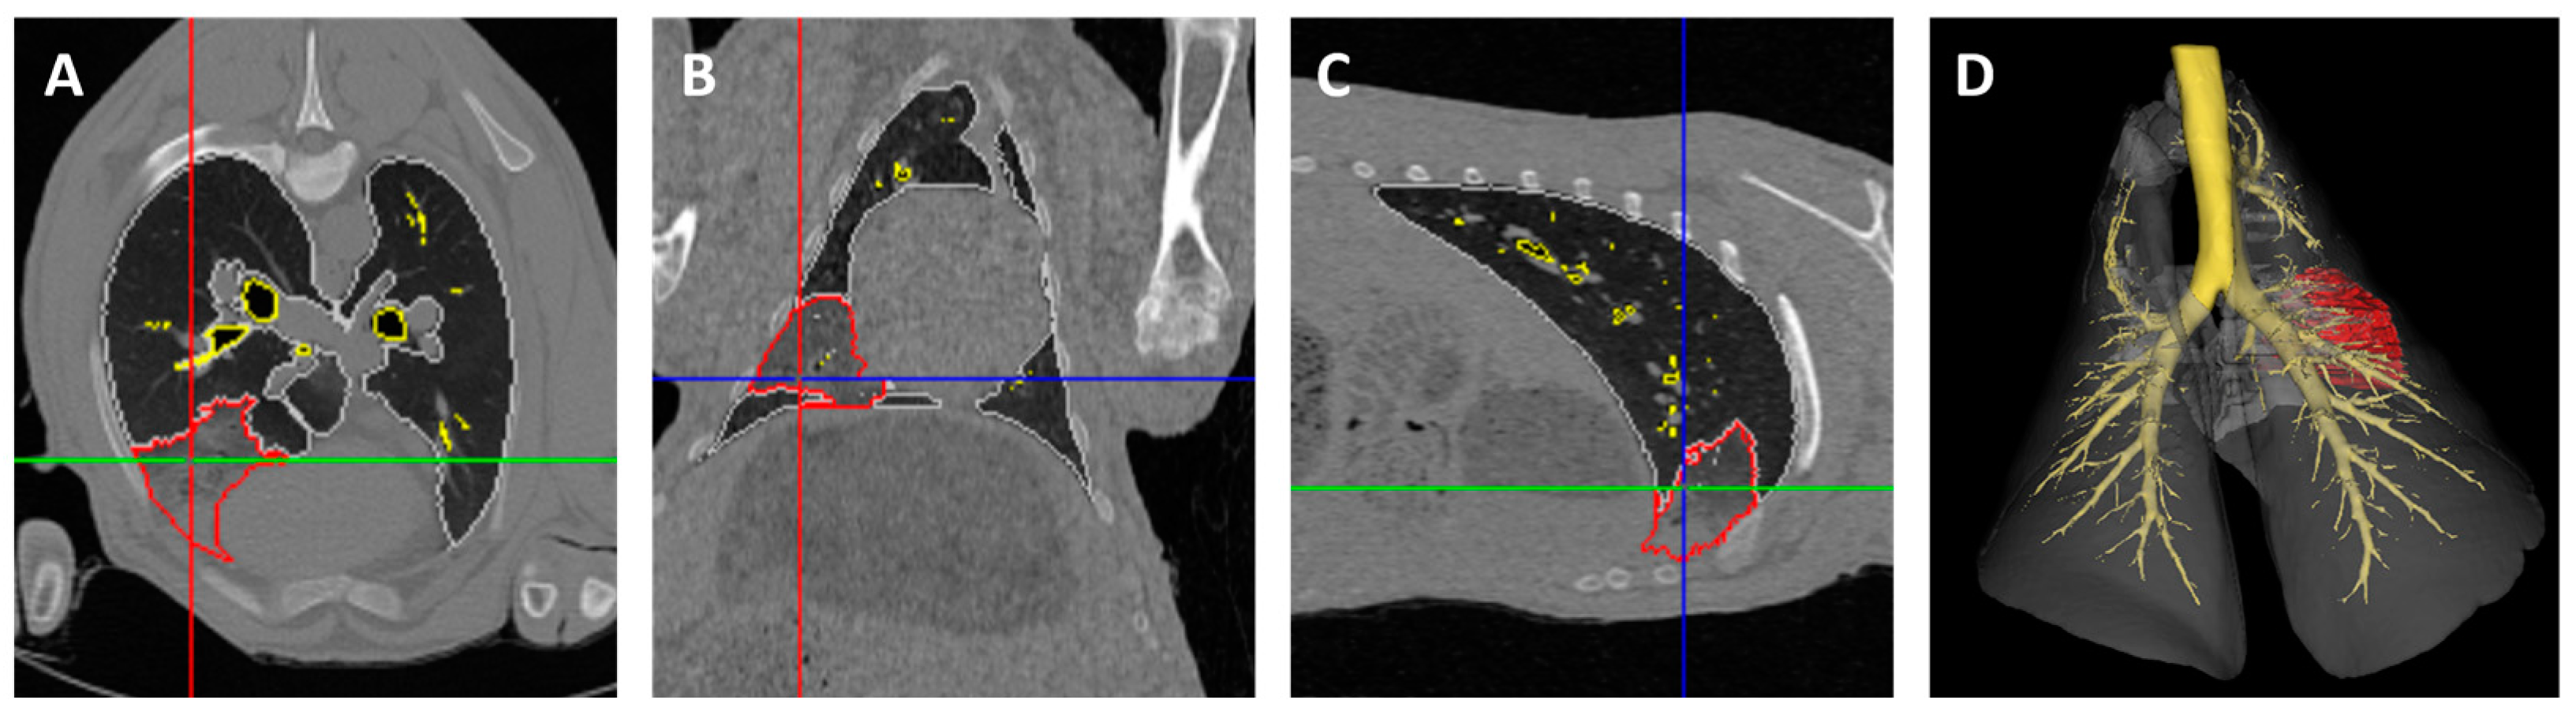

2.5. Computed Tomography Scanning

2.6. Bronchoscopy

2.9. CT Image Analysis

2.10. Statistical Analysis and Calculation of Tumour Volumes

3.3. Ultrasound and CT Are Able to Identify Changes Consistent with OPA Diagnosis

3.4. OPA Tumour Growth Rates Are Variable but Can Be Rapid